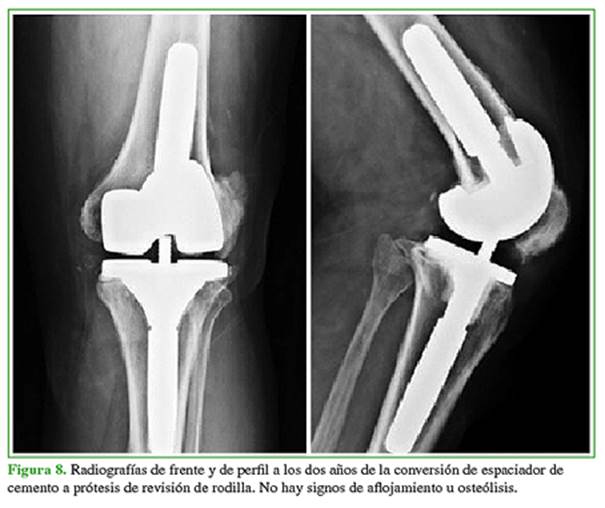

En la actualidad, el paciente no tiene infección según los parámetros clínicos y de laboratorio, camina sin limitación y sin asistencia; no se observan signos radiográficos de aflojamiento de la prótesis (Figura 8) y la flexo-extensión es de 0-120° (Figura 9).